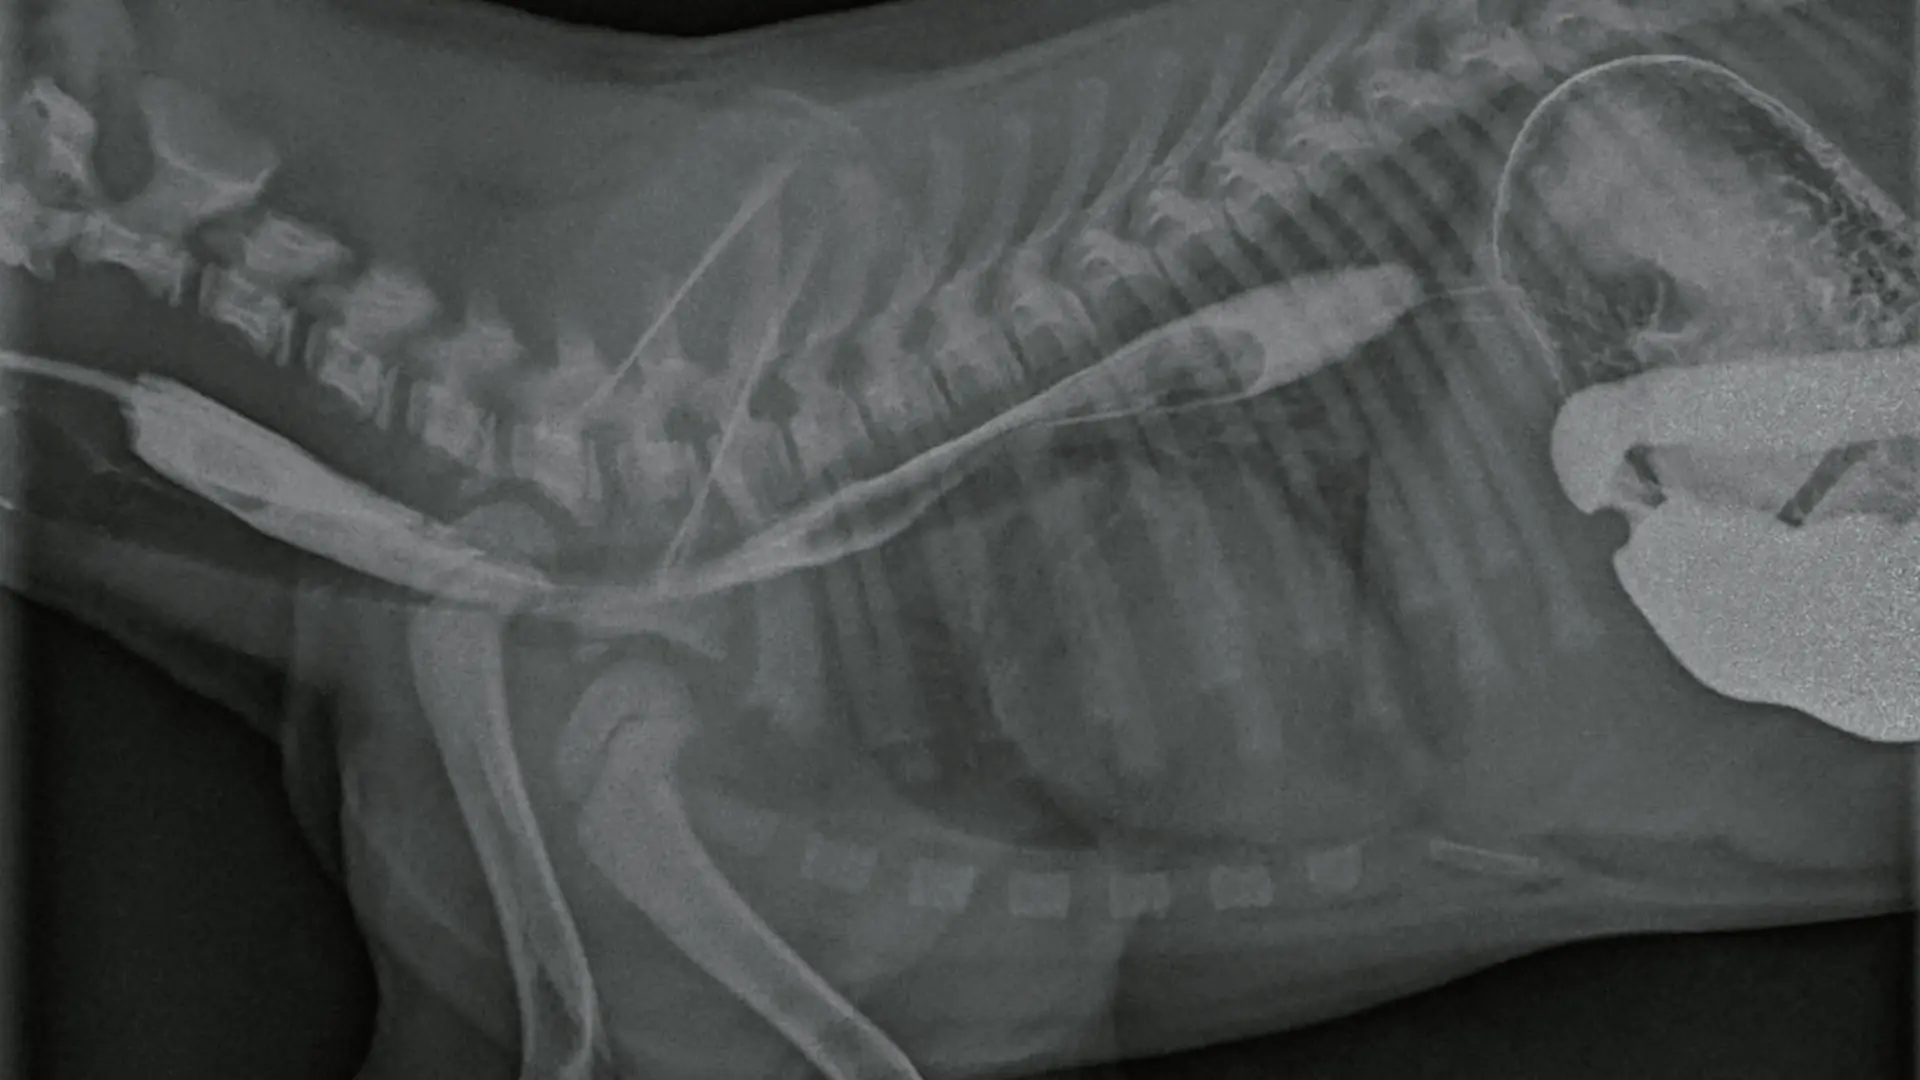

Akciğer Görüntüleme

Abdominal Görüntüleme

Oral kontrast maddesi

Torasentez örnekleme